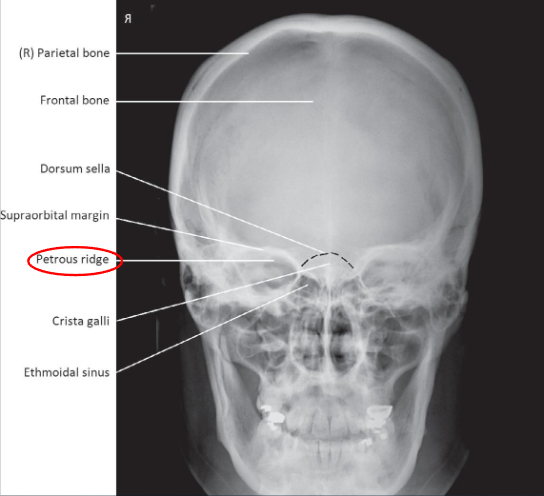

PA/PA axial (Caldwell) skull

PA skull image criteria

evidence of proper collimation

entire cranial perimeter showing three tables of squamous bone

no rotation:

equal distance from lateral borders of skull to lateral border of orbits

symmetric petrous ridges

petrous ridges fill orbits

penetration of frontal bone without excessive density of lateral borders of skull

PA axial (Caldwell) skull image criteria

petrous ridges demonstrated in lower third of orbits